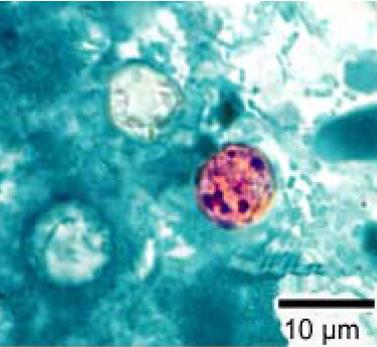

cyclospora cayetanensis oocysty

cyclospora cayetanensis oocysty